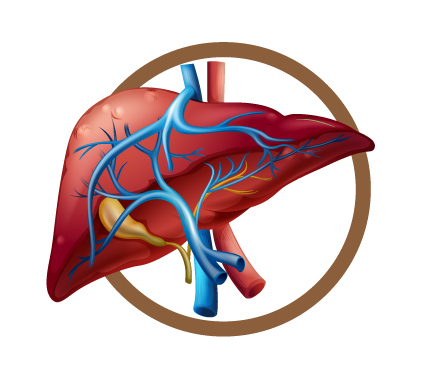

Causas del Hígado graso

Se conocía, por lo general que los hombres que consumían bebidas alcohólicas de forma recurrente sufrían a largo plazo de cirrosis. Sin embargo, en los últimos años es muy común en las citas médicas, ver mujeres con cirrosis por causa del hígado graso.

Incluso, muchas de ellas nunca han consumido bebidas alcohólicas. Hasta los niños menores de 12 años presentan esteatosis hepática.

El diagnostica el grado de hígado graso a través de una ecografía, también lo relaciona con los síntomas que presenta el cuerpo. Por ejemplo, si al comer sientes malestares estomacales, diarreas esporádicas, dolor abdominal, picazón al cuerpo o escamas en las manos.

Se asocian los síntomas con los resultados de las enzimas hepáticas. En el cuarto grado el hígado comienza a tener estructuras que se comienzan a dañar, y termina secándose en forma de pasa.

El hígado produce hormonas, defensas, vitamina k. Por eso, es tan importante hacer una buena prevención, porque no existe mejor medicamento que la prevención.

El hígado graso si es reversible, la cirrosis no.